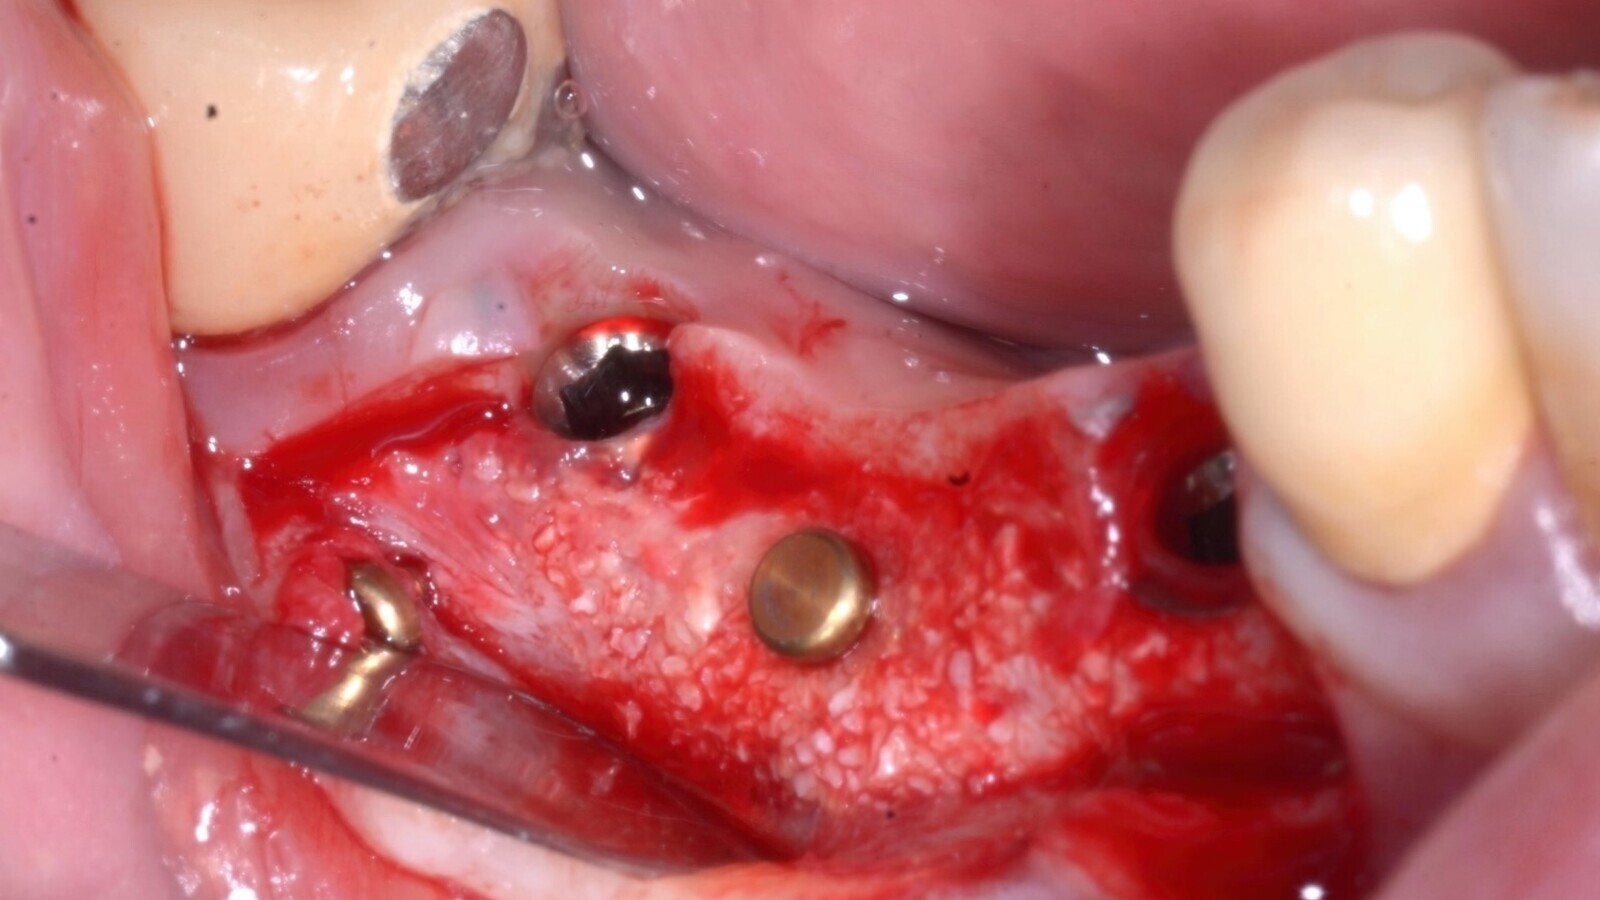

A los 4 meses de la ROG, el aspecto clínico mostraba una excelente cantidad de hueso recién formado y bien vascularizado (Fig. 10).

Fig. 10. Reapertura a los 4 meses que muestra la excelente cantidad de hueso recién formado y la buena vascularización del sitio, signo de hueso vital y maduro. El incremento horizontal es de 3 mm.

La lámina cortical se había remodelado completamente en hueso nuevo y se extrajeron los pernos que la habían inmovilizado. Se aplicaron tornillos de cicatrización para preparar el tejido blando (Fig. 11) para la prótesis definitiva. Dos meses más tarde se colocó un puente fijo de cerámica de 3 unidades, con los pilares 44 y 46 colocados.